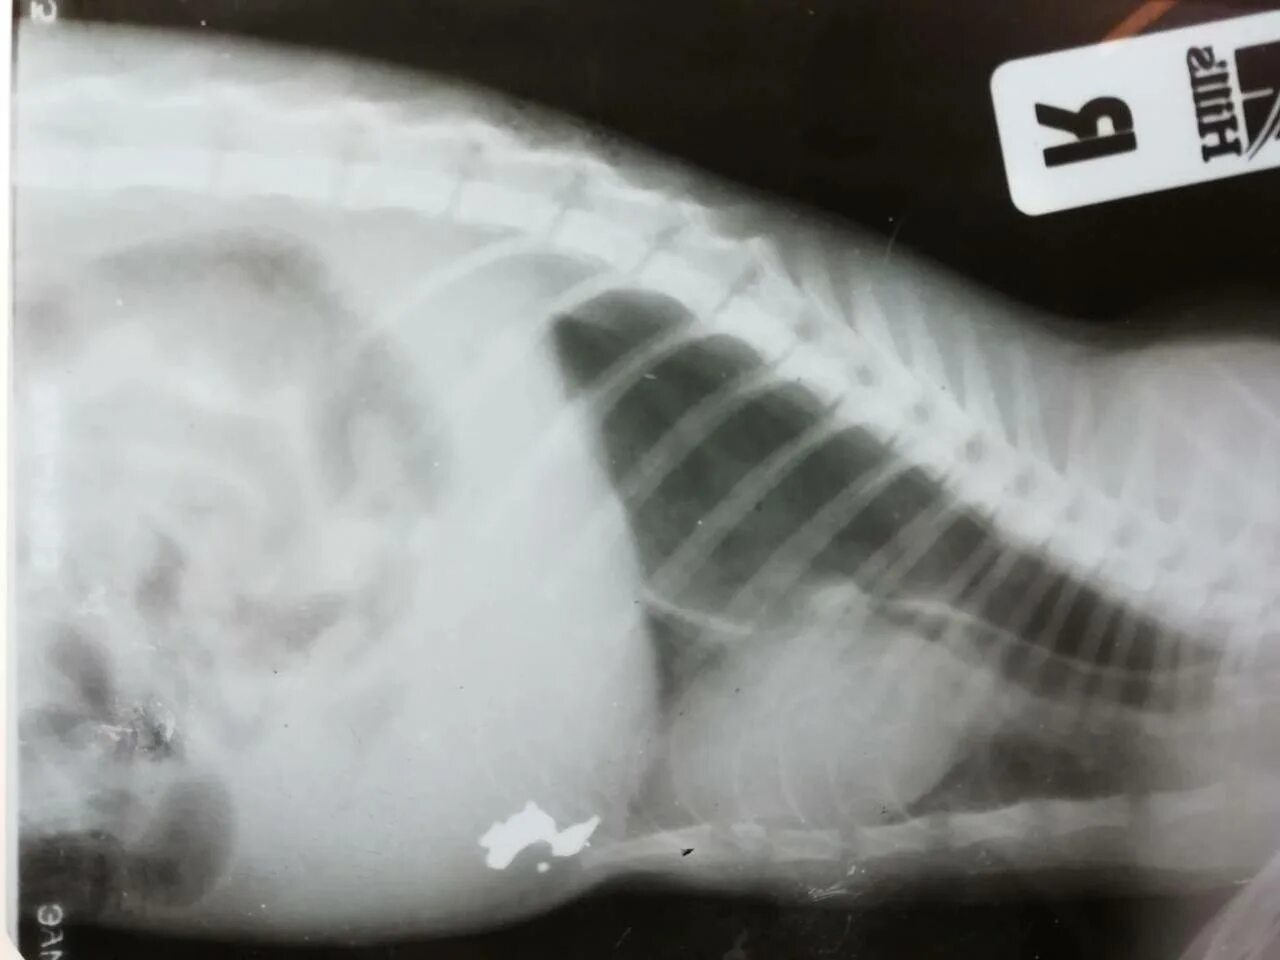

Делала рентген при беременности